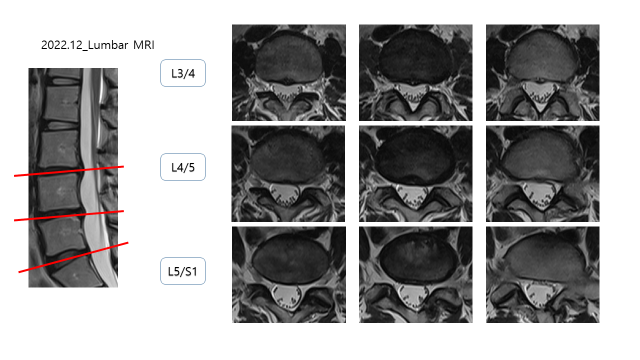

2018년도 MRI 상에서 디스크 탈출 소견이 있었음

L3/4 : DDD, Disc herniation

L4/5 : DDD, Disc protrusion

L5/S1 : bulging disc

이전에 촬영한 MRI와 비교를 하였을 때, 디스크 돌출/탈출 된 부분이 줄어든 것을 확인 할 수 있음.